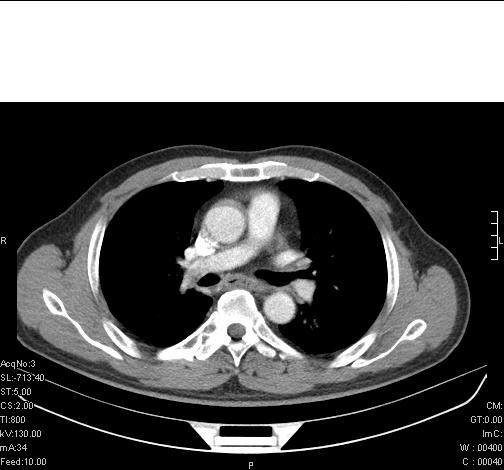

标题: CT6685:右肺阻塞性炎症,增强CT。

前几天,发了患者的平扫片,患者抗炎一周后增强扫描。右中叶病灶吸收明显,但下叶病灶未见明显吸收。右肺门可见结节影,看来凶多吉少

右肺下叶支气管管腔狭窄,管壁增厚,右下肺见斑片状高密度影,考虑右侧肺门中心肺癌伴阻塞性肺炎

右肺下叶支气管壁明显增厚,考虑癌症并阻塞性炎症、肺门淋巴结肿大

考虑右肺癌并阻塞性炎症、肺门淋巴结肿大

右肺下叶支气管壁不规则增厚,右肺下叶有斑片状影分布。考虑右肺中央型肺癌伴右肺下叶阻塞性改变。建议支纤镜检查。平扫比增强较好显示了病变情况。

右主支气管狭窄,管壁增厚。考虑右中心性肺ca伴阻塞性肺炎。

既然抗炎治疗有效,可继续治疗;右肺下叶支气管管腔狭窄,管壁增厚,右下肺见斑片状高密度影,右侧主支气管后见结节影(淋巴结?),肺癌不能排出。